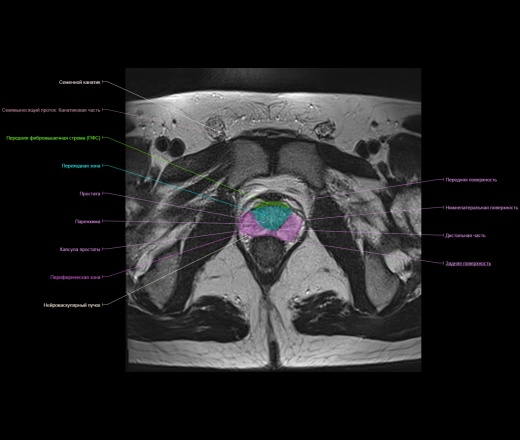

Представленный материал носит обучающий характер, не стал размещать в разделе Презентации, из за отсутствия вьюера с возможностью именно прокручивать изображения как на рабочей станции.

https://www.imaios.com/ru/e-Anatomy/Grudnaya-kletka-bryushnaya-polost-taz/Muzhskoj-taz-MRT

https://radiopaedia.org/cases/normal-prostate-mri

http://event.medradiology.moscow/d/1387577/d/mrt_predstatelnoy_zhelezy.pdf

Надписи очень плохо видно, разместил в разделе Презентации там видно получше.